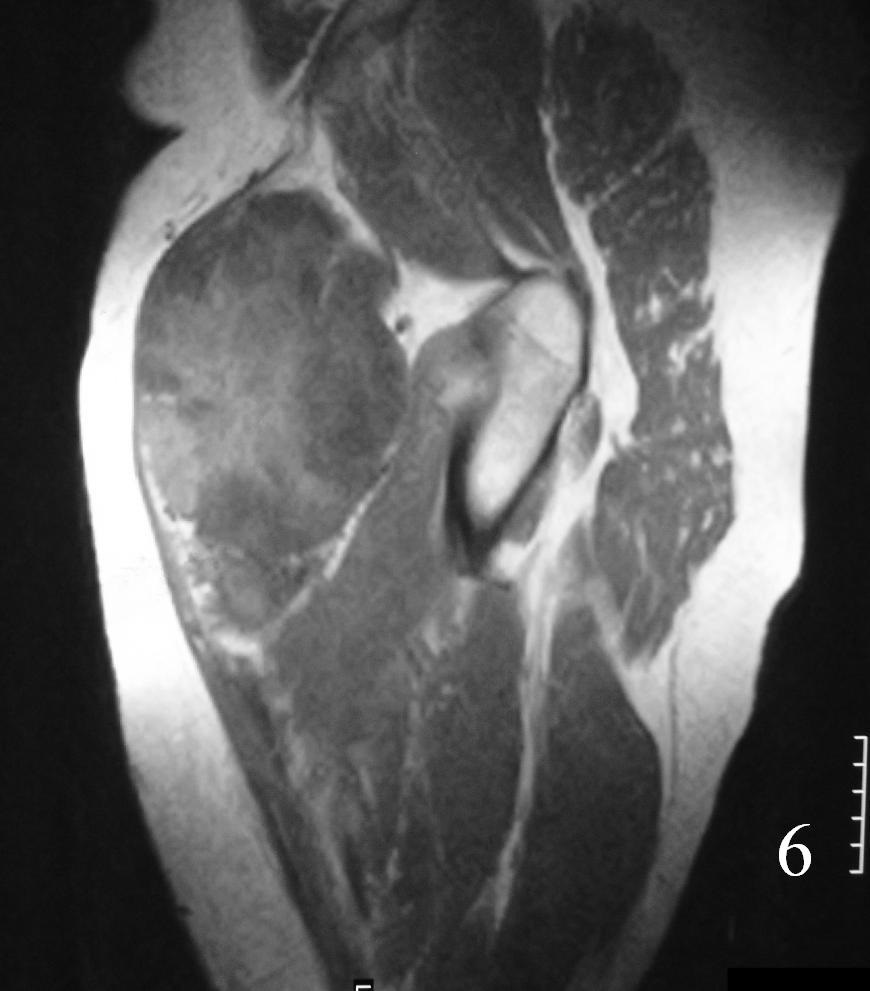

MRI (Fig. 3-7)

Fig. 6

Fig. 3-7 Axial MRI of the lower extremity shows an extraskeletal soft tissue chondrosarcoma in different sequences with and without contrast (Fig. 3, 4, 5). Sagittal MRI (Fig. 6, 7) T1 with-without contrast demonstrates enhancement of the mass